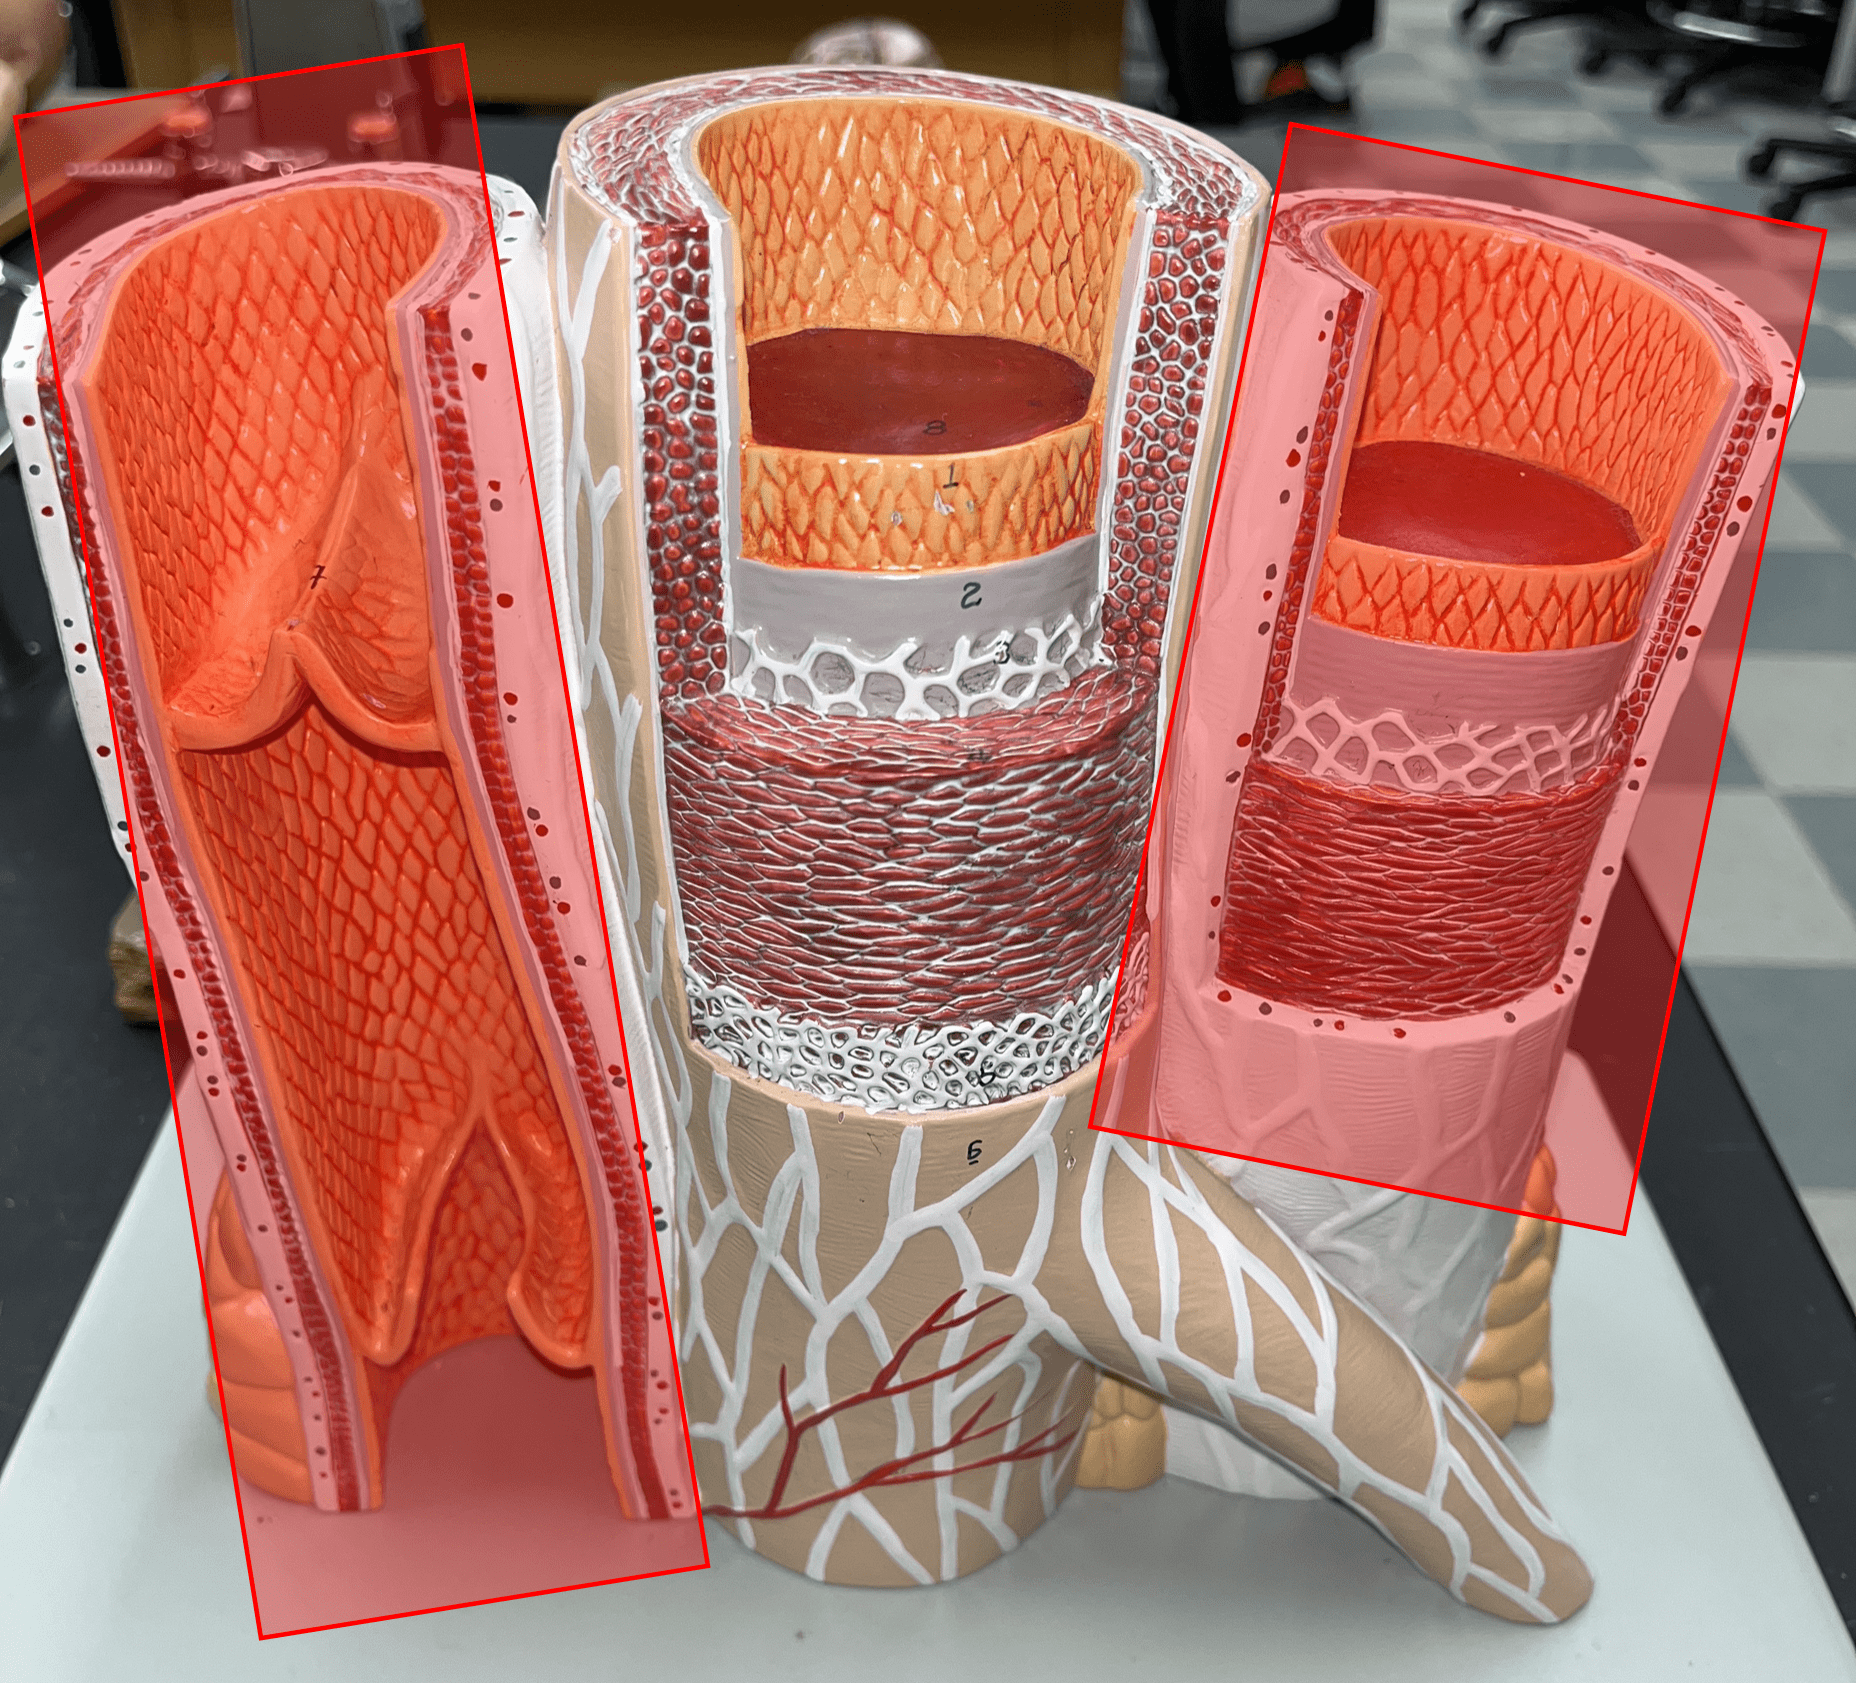

Study Analytics

|---|

No study sessions yet.

104 Terms

1

New cards

artery

• Transports blood away from the heart.